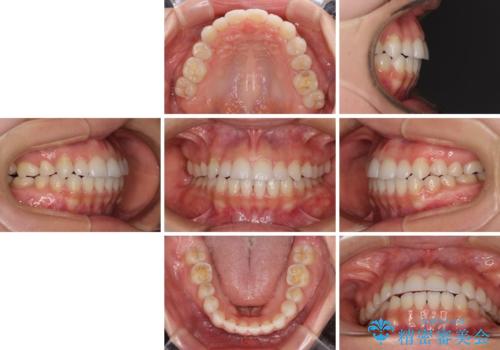

補助装置を事前に使用したことで、あっという間に八重歯が改善し、ハーフリンガルにしては1年半もかからずに治療を終えることができました。

- 前歯のデコボコや八重歯、舌癖による開咬を気にして来院された患者様です。

目立たない装置を希望されたので、上顎が裏側装置のハーフリンガルを選択し、上顎小臼歯1本を抜歯して、補助装置を併用して矯正治療を行うこととしました。